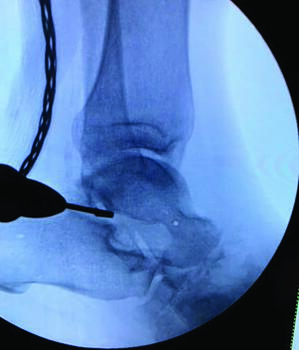

Distraction osteogenesis for limb length discrepancy secondary to hindfoot and/ or ankle Charcot neuroarthropathy is also an option. If no distal tibial angular deformity is present, one can make a corticotomy at the distal tibial meta-diaphyseal junction.26 One may initiate this through a medial small incision, with care taken to protect the neurovasculature posteriorly, with the aid of a low-speed, high-torque burr with irrigation. Once the corticotomy is complete, the site is distracted and intraoperative fluoroscopy can verify completion of corticotomy and maintained alignment of the distal extremity. Incremental lengthening then ensues after an appropriate latency phase, through the use of strut adjustments followed by an appropriate consolidation phase.